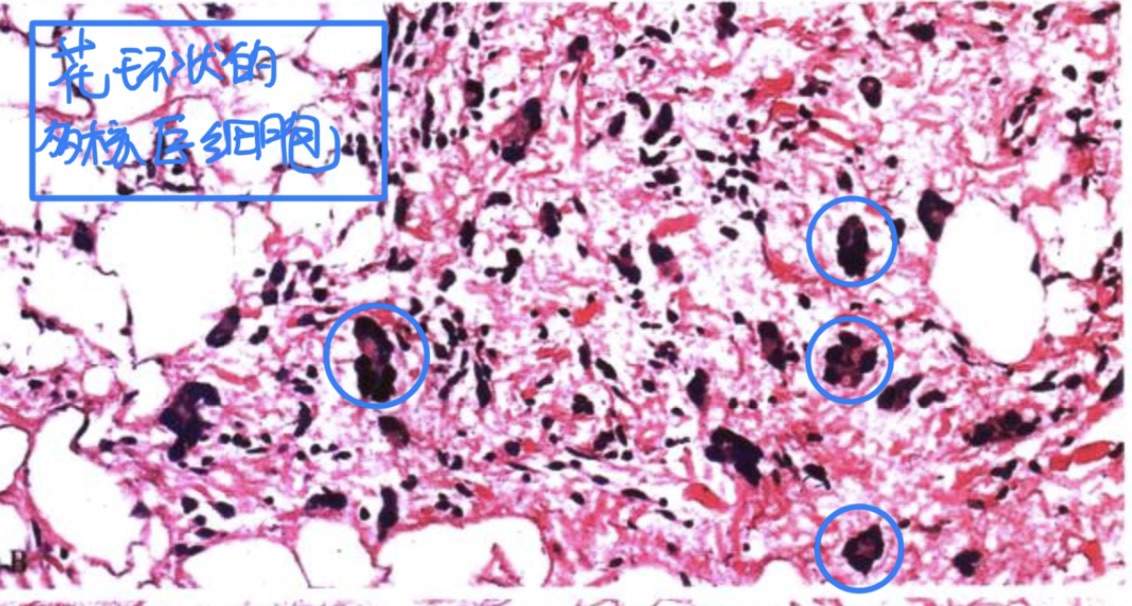

2、多形性脂肪瘤

选择它是因为花环状的多核瘤巨细胞。

诊断公式=梭形细胞脂肪瘤+花环状的多核瘤巨细胞,镜下如图: